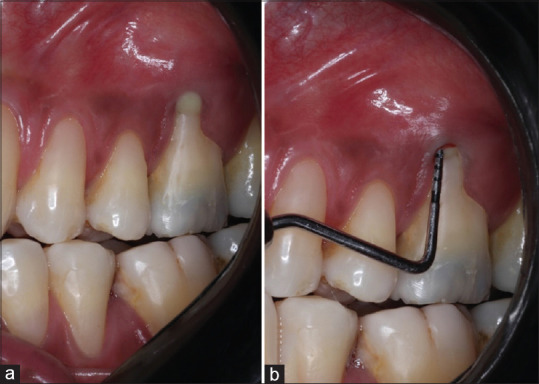

牙齿分叉缺陷的牙周治疗是具有挑战性的,因为该区域的复杂解剖结构。切除技术,如根切除,可以有效地治疗牙齿缺损,如果有适当的指示,可以导致令人满意的存活率和良好的预后。本报告描述了使用根切除结合再生手术治疗上磨牙II级分叉缺陷。再生过程包括使用冻干骨移植物结合使用胶原膜和结缔组织移植物。24个月的随访证明了治疗的成功,临床附着水平增加,探测袋深度减少,断层图像显示新硬膜层的形成。一个健康和稳定的牙周组织可以通过正确的应用更保守的技术来保护牙齿。

Periodontal treatment of teeth with furcation defects is challenging due to the complex anatomy of the area. Resective techniques, such as root resection, may be effective in managing teeth with this defect if appropriately indicated and can lead to satisfactory survival rates associated with a favorable prognosis. This report describes the treatment of a Class II furcation defect in an upper molar using root resection combined with regenerative procedures. The regenerative procedure involved the use of a lyophilized bone graft combined with the use of a collagen membrane and a connective tissue graft. The 24-month follow-up demonstrated the success of the therapy, with a gain in clinical attachment level, a reduction in probing pocket depth, and a tomographic image showing the formation of new lamina dura. A healthy and stable periodontium can be achieved through the correct application of more conservative techniques aimed at preserving the dental element.